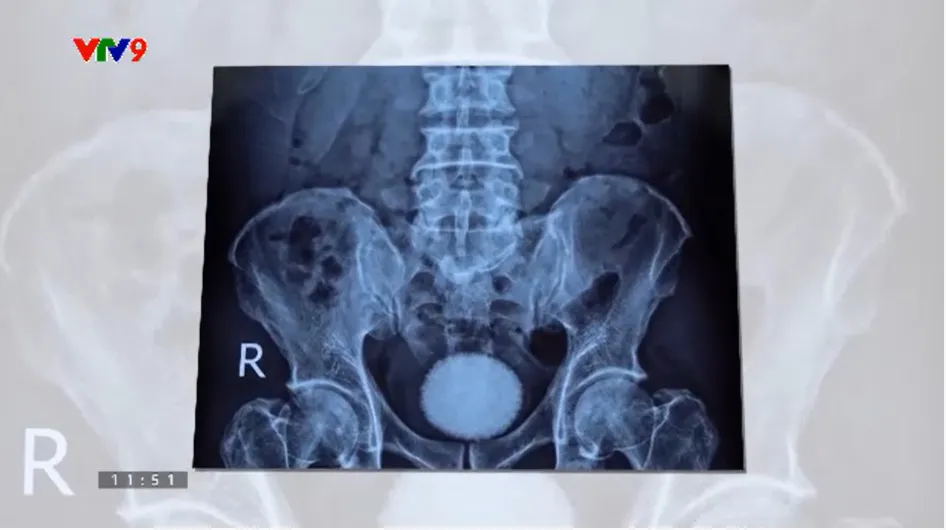

VTV9.vtv.vn - Các bác sĩ Khoa Ngoại tiết niệu (Bệnh viện Đa khoa Xuyên Á - Tây Ninh) vừa phẫu thuật thành công lấy viên sỏi bàng quang kích thước lớn, tương đương quả trứng ngỗng (DVE) cho bệnh nhân nam 50 tuổi.

Người bệnh nhập viện với tình trạng đau bụng dưới, tiểu khó, tiểu nhiều lần kéo dài. Qua thăm khám lâm sàng, siêu âm và chụp X-quang, các bác sĩ phát hiện: trong bàng quang có viên sỏi kích thước khoảng 60x40 mm, nên chỉ định phẫu thuật. Sau ca mổ, viên sỏi đã được lấy ra an toàn, sức khỏe bệnh nhân ổn định và đang tiếp tục được theo dõi điều trị.